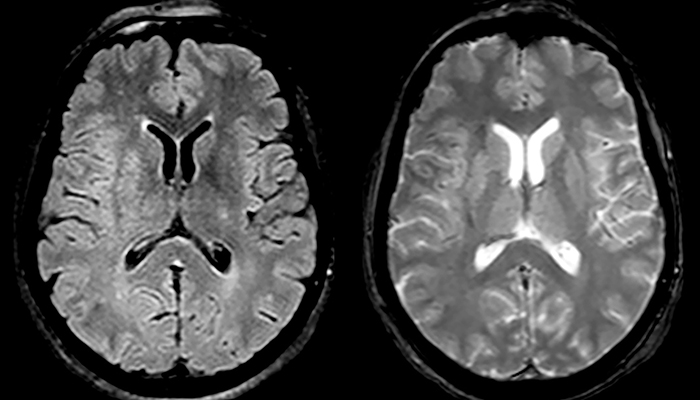

“Ingenia 3.0T provides us very good image quality with high SNR, even if we push the resolution. For example, in FLAIR images we may have an isotropic resolution of 0.9 mm. Ingenia allows us to use 3D T1 TSE with BrainView, which has a better sensitivity than 2D spin echo imaging[2] and 3D gradient echo imaging. Ingenia also provides highly reproducible exams, which is important in MS imaging so that follow-up exams at different time points are done the same way.”

For MS imaging in the brain, Dr. Savatovsky uses 3D FLAIR as the basic sequence to visualize the lesions and assess the situation and lesion load. “We count the lesions in each location to determine if the criteria of the disease are fulfilled. We use a T2-weighted sequence because our neurologists are used to it. We compare the lesion load on FLAIR with a 3D T1 post-contrast sequence to help us determine whether lesions are old or new. We typically administer the contrast before the patient enters the machine because it shortens the examination time and allows to visualize active lesions that tend to be more visible after several minutes. When a differential diagnosis is difficult, we add sequences such as susceptibility imaging, because some focal MS lesions have a small vein in the center[3].”

“In France, every stroke is usually imaged with MRI, not CT, even for emergency treatment.” “In France, stroke is usually imaged with MRI, not CT, even for emergency treatment. This is because MRI helps us directly visualize ischemia in the acute phase, but can also help rule out differentials such as MS and hematoma. In addition, we can assess the intracranial and extracranial vessels during the same examination,” says Dr. Savatovsky.

“Ingenia provides great flexibility in the parameters setting. We can tune a sequence the way we want,” says Dr. Savatovsky. “For example, in a stroke exam we use a FLAIR sequence of about two minutes instead of the four-minute FLAIR we use for MS. The diffusion is 30 seconds, the T2*-weighted scan is 30 seconds, the angiography scan time is less than one minute. Ingenia is a great scanner in that situation; even with these fast sequences we can achieve good images with good SNR. When the first sequence tells us that it’s not an ischemic stroke but a hemorrhagic stroke, we may switch to a time-resolved angiography to look for vascular malformations and venous thrombosis.

“Every center is different, but for me the ideal protocol for stroke includes diffusion weighted imaging, FLAIR, and fast susceptibility imaging,” says Dr. Savatovsky. “Our fast susceptibility weighted imaging takes 50 seconds, so it’s as fast as T2*-weighted imaging. It visualizes hemorrhage but also the clots. We also do 3D MR angiography that provides information on cervical and brain vessels. If the patient does not need immediate treatment, or if additional information is needed to decide on treatment, we might also add perfusion imaging and post-contrast T1-weighted imaging.”